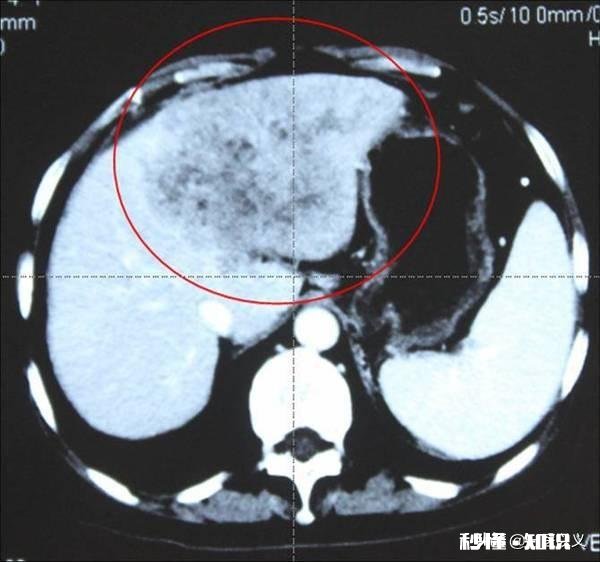

肝癌术后复发率较高肝癌在老百姓心里是一个很可怕的癌症,因为肝癌太厉害,得了肝癌的人 , 基本都不会活很久 。目前肝切除术仍是治疗肝癌的首选方法 。肝癌切除确实一定程度增加了患者的生存期 , 但是,并不是进行了手术就万事大吉,因为肝癌术后复发的情况还是比较常见的,这也是有些患者不愿意进行手术的原因 。那么肝癌的术后复发率有多恐怖,请记住以下数据:肝癌切除术后3年内的复发率为50%左右;肝癌切除术后5年内的复发率为70%左右 。而且,患者肝癌复发后,一般再次治疗的效果不佳,虽然还可以进行肝癌射频消融术、肝癌介入栓塞术治疗,但是,基本无痊愈可能 。

文章插图

肝癌复发率高的原因(1)肝癌自身因素

①.这可能与肝癌早期转移有关,肝脏血运丰富,早期经血运转移情况较多;

②.与肝癌肿瘤的数量有关 , 研究证明肝肿瘤的数量越来,预后越差 , 手术后复发率乐高;

③.与肿瘤的形态、大小相关,一般体积较大的肿瘤、以及肝癌形态差突出包膜,都是术后复发的高危因素;

④.与肝癌是否侵犯血管、有无癌栓形成有关 , 如果已经存在肝脏静脉血管的侵犯以及癌栓的形成,那么术后复发风险极高;

⑤.与肝癌是否有包膜相关 , 有包膜的肝癌肿瘤一般术后复发率较无包膜肝癌发生率低 。